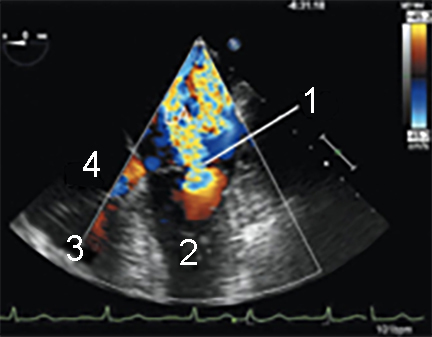

Cardiac 2 Valves Vena Contracta 2 Image Vena Contracta of Mitral Regurgitant (MR) Jet Left Ventricle (LV) Right Ventricle (RV) Right Atrium (RA)